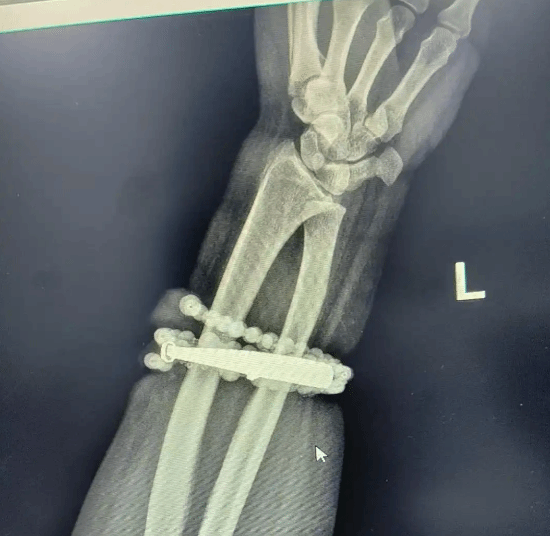

据媒体报道,33岁的龚女士因长期不当佩戴首饰,导致银手镯与串珠完全嵌入皮肤,引发严重软组织感染,不得不紧急就医。

据龚女士自述,她佩戴这只银手镯和串珠已近十年,几乎从未摘下。随着体重逐渐增加,她开始感到手腕皮肤被越勒越紧,但始终未加重视。直到近期,手腕部位疼痛加剧,出现明显红肿并伴有脓液渗出,她才意识到手镯与串珠已部分“长”进肉里,无法自行取下。

最终,医生经过一个多小时的精细手术,成功将手镯与串珠从她手腕中完整剥离,并进行清创引流,控制住了感染,使患者转危为安。